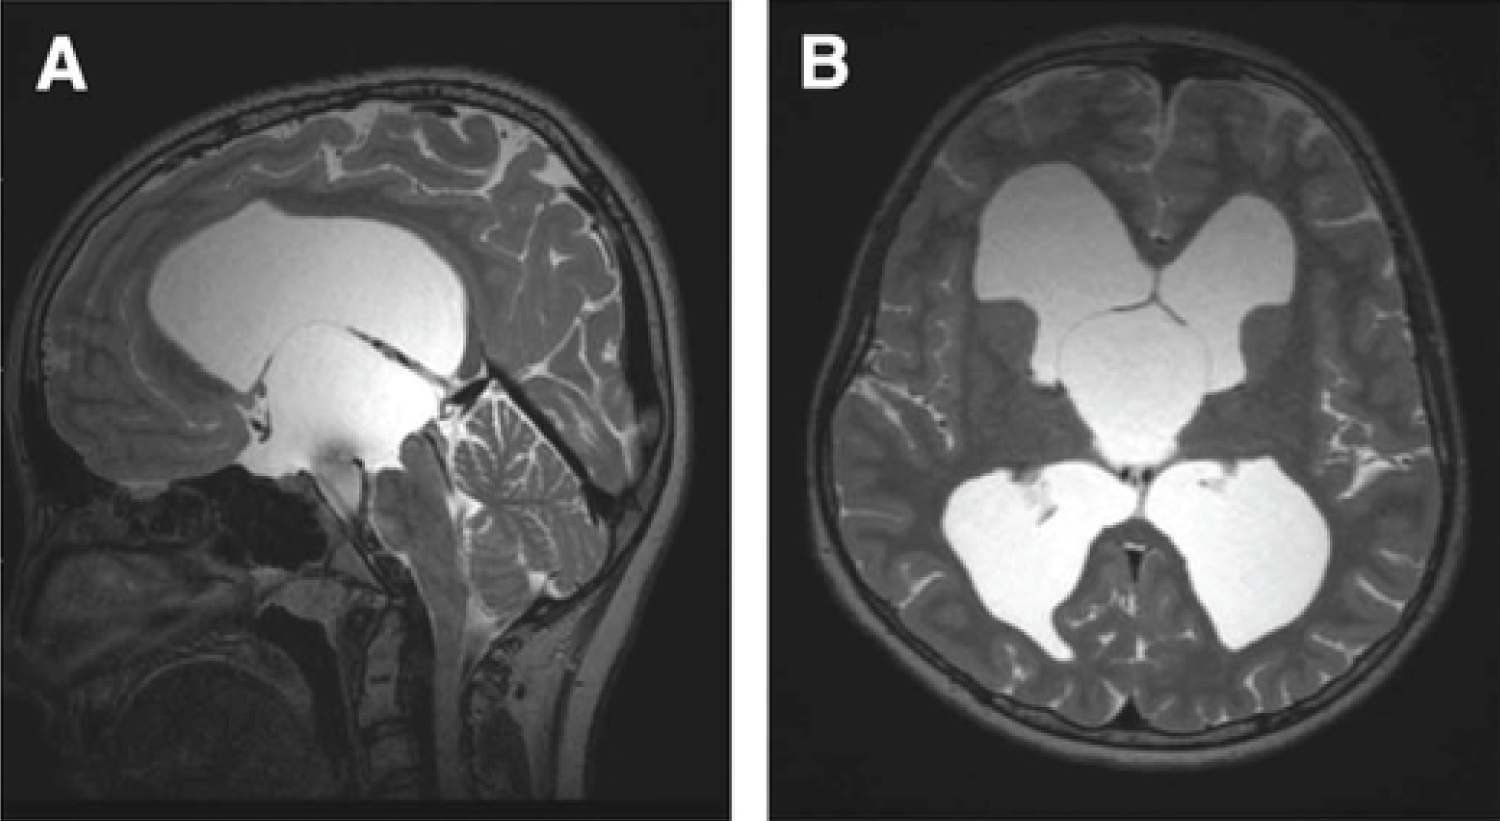

The MRI after surgery showed a decrease in the size of the ventricles. Unfortunately the ventricles continued to dilate and on the MRI of the 19th day of life, there was a stability in size of the cyst but also a clear tetraventricular hydrocephalus due a residual mass effect on the ambiens cistern and the pons.

We then decided to place a ventriculoperitoneal shunt.

The next MRI showed a reduction of the size of the ventricles and an absence of mass effect of the cyst. The patient was discharged on day....